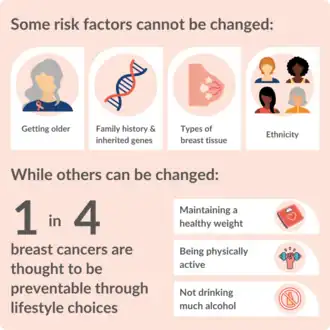

Risk factors for developing breast cancer include obesity, a lack of physical exercise, alcohol consumption, hormone replacement therapy during menopause, ionizing radiation, an early age at first menstruation, having children late in life (or not at all), older age, having a prior history of breast cancer, and a family history of breast cancer.[1][2][9] About five to ten percent of cases are the result of an inherited genetic predisposition,[1] including BRCA mutations among others.[1] Breast cancer most commonly develops in cells from the lining of milk ducts and the lobules that supply these ducts with milk.[1] Cancers developing from the ducts are known as ductal carcinomas, while those developing from lobules are known as lobular carcinomas.[1] There are more than 18 other sub-types of breast cancer.[2] Some, such as ductal carcinoma in situ, develop from pre-invasive lesions.[2] The diagnosis of breast cancer is confirmed by taking a biopsy of the concerning tissue.[1] Once the diagnosis is made, further tests are carried out to determine if the cancer has spread beyond the breast and which treatments are most likely to be effective.[1]

Actions to prevent breast cancer include not drinking alcoholic beverages, maintaining a healthy body composition, avoiding smoking and eating healthy food. Combining all of these (leading the healthiest possible lifestyle) would make almost a quarter of breast cancer cases worldwide preventable.[116] The remaining three-quarters of breast cancer cases cannot be prevented through lifestyle changes.[116]